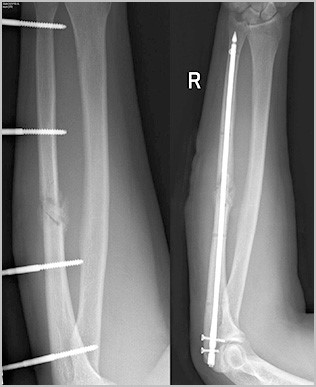

Для лечения переломов предплечья используется различные разновидности фиксаторов. Например, блокируемые интрамедуллярные (внутрикостные) стержни используются при переломах диафизов лучевой и локтевой кости и позволят достигнуть стабильной фиксации при минимальной травме мягких тканей.

Чаще остальных фиксаторов, при переломах лучевой и локтевой кости используются пластины и специальные винты. Остеосинтез перелом лучевой и локтевой кости является «золотым стандартом» в травматологии.

Современные пластины и винты позволяют зафиксировать отломки в области перелома в правильном с анатомической точки зрения положении, а также стабильно удержать это положение до сращения перелома.